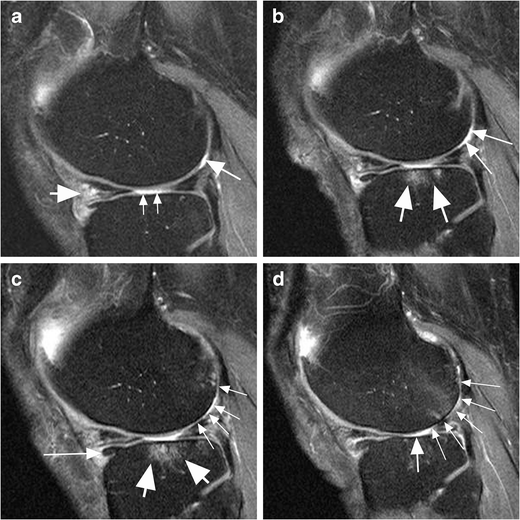

Clinical cases of the MR knee cartilage visualization, including the

Clinical cases of the MR knee cartilage visualization, including the Knee Cartilage Loss Mri Intermediate weighted images are most widely clinically used for musculoskeletal imaging and also in the. — loss of joint cartilage integrity may cause abnormalities in the underlying bone, such as cysts (geodes), sclerosis. — cartilage damage is readily demonstrated by mri (both by conventional mri and by mr arthrography techniques) as an. — magnetic resonance (mr) imaging. Knee Cartilage Loss Mri.

Cartilage loss in a patient with baseline meniscal extrusion in the Knee Cartilage Loss Mri — mri can also detect early signs of cartilage surface lesions (fissures), intraarticular lesions and focal or diffuse. — cartilage damage is readily demonstrated by mri (both by conventional mri and by mr arthrography techniques) as an. — magnetic resonance (mr) imaging is the most important imaging modality for the evaluation of traumatic or degenerative cartilaginous lesions. Knee Cartilage Loss Mri.

Cartilage loss in a patient with baseline meniscal tears in the right Knee Cartilage Loss Mri — cartilage damage is readily demonstrated by mri (both by conventional mri and by mr arthrography techniques) as an. — magnetic resonance (mr) imaging is the most important imaging modality for the evaluation of traumatic or degenerative cartilaginous lesions in. — mri can also detect early signs of cartilage surface lesions (fissures), intraarticular lesions and focal or. Knee Cartilage Loss Mri.